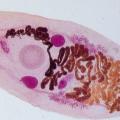

На текущей неделе, в диагностический отдел была доставлена печень крупного рогатого скота с целью проведения исследований на наличие возбудителей паразитарных болезней.     В результате лабораторных испытаний, специалистами отдела выявлены отклонения от физиологических норм выраженные в увеличении печени, изменении её цвета на желтовато-коричневый, расширении желчных ходов с признаками атрофии и некроза, заполнении желчных протоков полужидкой массой, содержащей большое количество личинок дикроцелиев, возбудителя дикроцелиоза жвачных.     Для справки.   Дикроцелиоз – паразитарная болезнь, вызываемая трематодой, поражающей, в основном жвачных животных, проявляющаяся нарушением работы желудочно-кишечного тракта, поражением печени, исхуданием, желтушностью слизистых, отеками подгрудка и снижением продуктивности. Могут болеть и другие животные, а также человек.      Своевременная лабораторная диагностика фекалий животных позволяет обнаружить возбудителей паразитарных болезней, а также контролировать качество дегельминтизации поголовья животных в хозяйствах